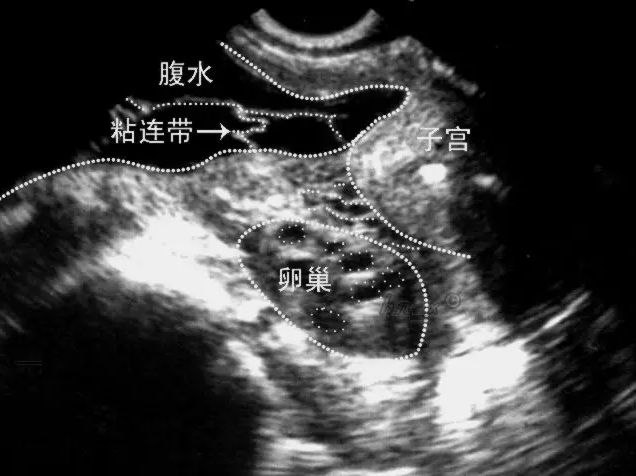

很多女性朋友來到醫院監測卵泡,排卵正常,但總是懷不上,偶有小腹下墜感覺,這種情況,您需要引起重視!因為您可能患有盆腔粘連!

盆腔黏連主要是指盆腔內的組織出現了細菌感染或者病毒感染,從而導致組織器官出現了炎癥的現象,由于盆腔黏連的出現,很有可能會導致患者出現子宮輸卵管炎,卵巢炎等等問題,由于這些疾病的原因,就有可能會導致患者的身體癥狀出現,比如患者可能會出現水腫,分泌物增多等等問題,如果不及時的進行控制,還有可能會誘發其他問題的出現,如影響輸卵管蠕動和絨毛擺動,無法正常拾卵,影響女性懷孕。